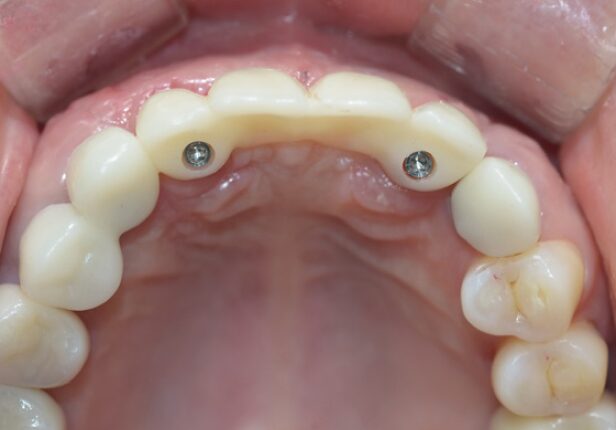

Temporary Crown

Before Final Crown placement

Final Crown

Temporary Crown after 1 month